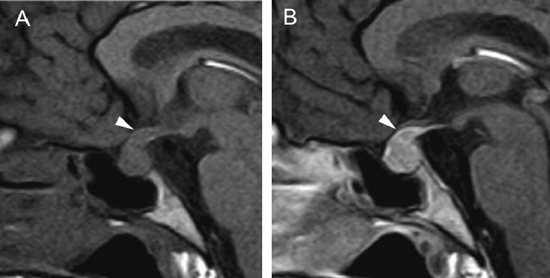

A diferencia de la tomografia computada, que emplea tubos de rayos X, la RM no utiliza radiaciones ionizantes, lo que es una ventaja a considerar en los pacientes pediátricos y en las mujeres embarazadas. La RM tiene una excelente resolución espacial y de tejidos blandos; por ejemplo permite precisar la presencia o ausencia de la neurohipófisis, lo que no es posible con la Tomografia Computada5-7. Con la TAC, con o sin medio de contraste yodado, es posible detectar microadenomas y macroadenomas pituitarios (Figuras 1A y 1B); sin embargo, en los macroadenomas puede ser difícil distinguir las relaciones del tumor con el quiasma óptico, o definir la invasión del seno cavernoso. Además, los artefactos producidos por amalgamas dentales deterioran las imágenes y la dificultad para lograr posiciones cómodas para los pacientes, con el fin de obtener cortes coronales directos, limitan la utilidad de la TAC.

Figura 1A y B. TAC con contraste yodado, corte coronal, muestra un microadenoma lateralizado a izquierda (punta de flecha). Control a los 2 años. TAC con contraste yodado, corte coronal, demuestra aumento de volumen del microadenoma, lo que es infrecuente de observar en clínica (punta de flecha).